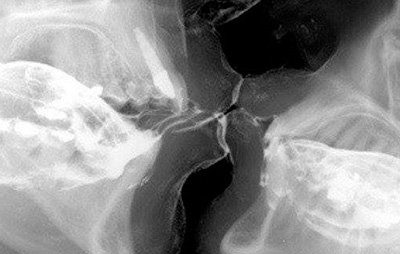

Bacio ai raggi x

Bacio ai raggi x In base al Protocollo Chirurgico applicato esistono diversi tipi di Tecnologie Disponibili. Nei nostri Studi applichiamo prevalentemente la metodica di Osteointegrazione a carico differito, al fine di rendere più Controllabile il Successo dell'Intervento Implantologico. Adottiamo dei Trattamenti di Superficie per i componenti a diretto contatto osseo, tecniche di rigenerazione dei Tessuti mancanti e di Mantenimento Igienico per rendere più adeguato il sito all'inserimento di queste strutture artificiali. Le metodiche di implantologia che utilizziamo prevedono principalmente le tre strategie chirurgiche usualmente applicate in Italia: con l'inserimento di radici artificiali al di sotto delle gengive, con il loro posizionamento prossimo alle mucose mantenendo il contatto visivo e con il posizionamento di strutture one-piece comprensive della componente esterna su cui viene applicato in poche ore il dente artificiale provvisorio.